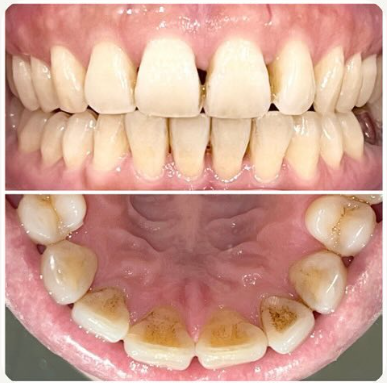

ステイン除去

BEFORE

AFTER

年齢:20代男性

治療内容:エアーフローによる歯の着色汚れ、ステイン除去

治療期間/通院回数:1回

費用: ステインコース 8,800円

リスク・副作用

①効果には個人差があり、着色汚れによっては一度に取りきれない場合があります。

施術後数時間以内に、着色効果の強いもの(コーヒー・紅茶・喫煙など)を摂取すると、歯に色素沈着が起こる可能性があります。

パウダーの刺激により歯ぐきから出血する可能性があります(痛みはほとんどありません)。